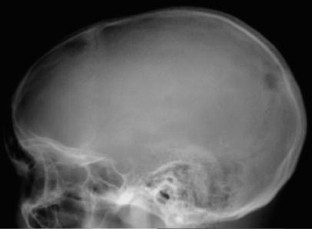

Calvarial tuberculosis: an unusual presentation (2007: 8b)

We describe a case of calvarial tuberculosis with an associated extra-dural collection. This presentation has rarely been reported in the literature and the magnetic resonance imaging features are not well documented.

Fig. 2